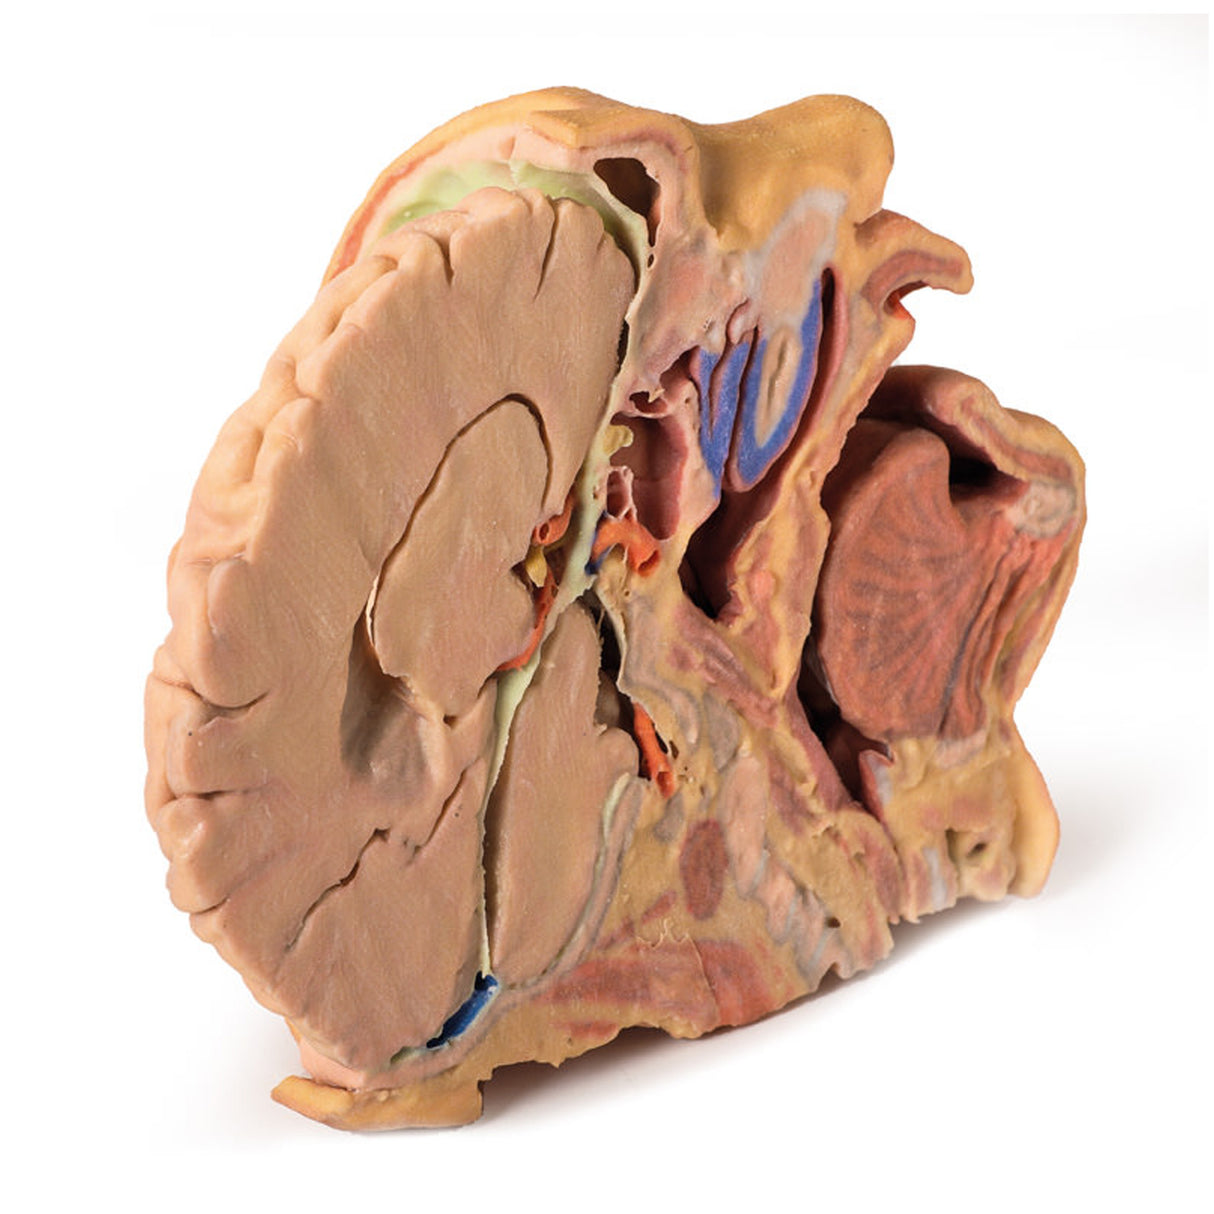

This 3D print provides a detailed view of head and neck anatomy, showing different structures depending on the perspective.

Lateral Face and Parotid Region

A window exposes the parotid region, with the pinna intact and the mastoid process revealed by reflecting the sternocleidomastoid (SCM). The parotid gland is removed to display hidden structures, including the posterior digastric, masseter muscle, and mandibular condyle in the TMJ. The external carotid artery (ECA) and its branches, internal jugular vein (IJV), hypoglossal, vagus, spinal accessory, and facial nerves are clearly visible. Facial dermatomes are illustrated via the trigeminal nerve branches.

Medial Surface and Key Vessels

The parasagittal section reveals the lateral ventricle, cerebral peduncle, posterior cerebral artery, and the tentorium cerebelli. The internal carotid artery in the cavernous sinus is shown lateral to the optic chiasm. Additional structures include the mouth, tongue, associated muscles, nasal cavity, nasopharynx, and cervical vertebrae.